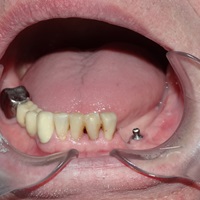

Hybrydowe podparcie protezy ruchomej na jednym implancie i jednym własnym zębie. Nie zawsze możemy osadzić u pacjenta dwa implanty. Przykłady hybrydowego podparcia protezy ruchomej na atachmentach opartych na własnym zębie i implancie.

Pacjent lat 68, po zawale mięśnia sercowego. Podczas reanimacji wyłamano ząb 43, będący zębem klamrowym szkieletu. Doszło do znaczącego ubytku tkanki kostnej. Osadzono implant, odbudowano brakujące tkanki kości i dziąsła. Pacjent zadowolony z hybrydowego zakotwiczenia protezy.